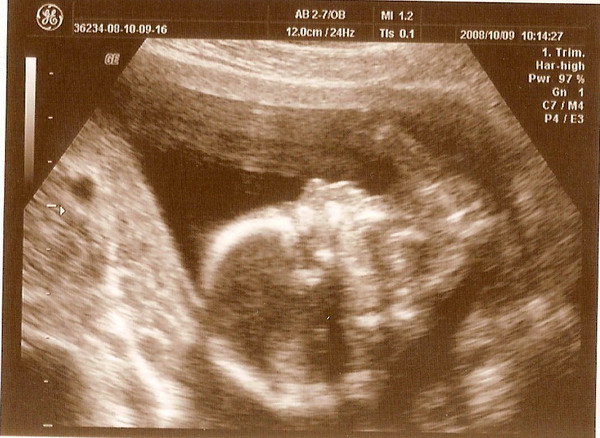

Kép

KISFIÚNK!!! feje

Tök jó volt az UH. Az eredményeink tökéletesek, minden rendben van. Az UH 25 percig tartott, mert rajtam, a tesómon, a dokin és az asszisztensen kívül még 7-en bent voltak, és a doki részletesen magyarázott nekik mindent. Így én is pontosan mindent megtudtam. És már van orvosom. Az a doki volt bent, akit meg akartam kérni, pedig nem is ő dolgozott ma az UH-ban. Csak engem vizsgált ő. TÖK JÓ!!! Örülök. Mondjuk kislánynak is ennyire örülnék!!! Annak örülök, hogy egészséges.